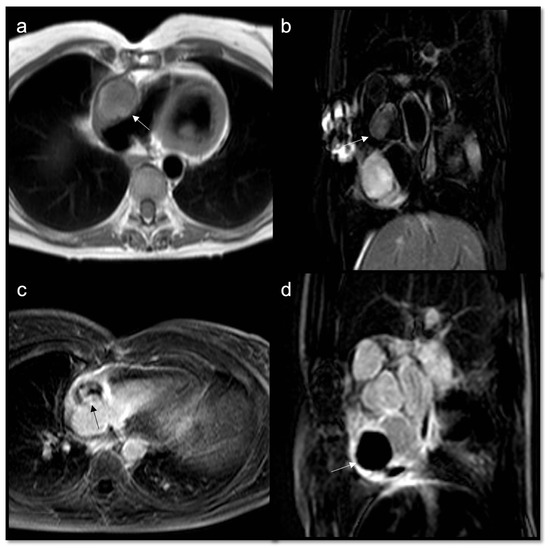

- Malignant masses often show heterogeneous enhancement; typically, angiosarcoma shows early avid enhancement as it is richly vascularized.

- Trombi due to their avascular nature appear non-enhanced.